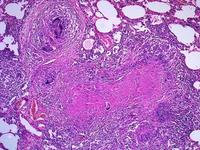

(8)肝臟 全身彌散性LCH常常侵犯肝臟,肝臟受累部位多在肝臟三角區,受累的程度可從輕度的膽灑淤積到肝門嚴重的組織浸潤,出現肝細胞損傷和膽管受累,表現肝功能異常、黃疸、低蛋白血症、腹水和凝血酶原時間延長等,進而可發展為硬化性膽管炎、肝纖維化和肝功能衰竭。

(9)有新出現的皮疹者應做皮疹壓片,如能做皮疹部位的皮膚活檢則更為可靠;有淋巴結腫大者,可做淋巴結活檢,有骨質破壞者,可做腫物刮除,同時將刮除物送病理,或在骨質破壞處用粗針作穿刺抽液,塗片送檢。